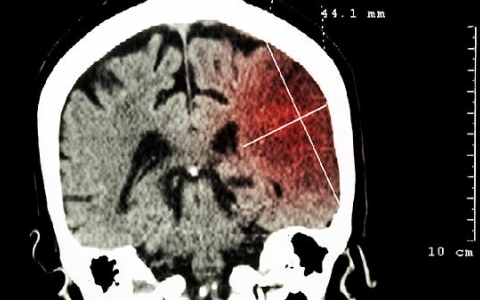

脑溢血重度昏迷严重吗?

脑溢血对于很多人来说是比较常见的一种身体疾病,一般好发于中老年人群,而引起脑溢血的原因有很多种,身体患有高血压或者是血脂粘稠都会容易导致出现脑溢血,在出现脑溢血